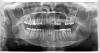

Marina87 Опубликовано 6 июля, 2013 Автор Поделиться Опубликовано 6 июля, 2013 Вот фото Ссылка на комментарий